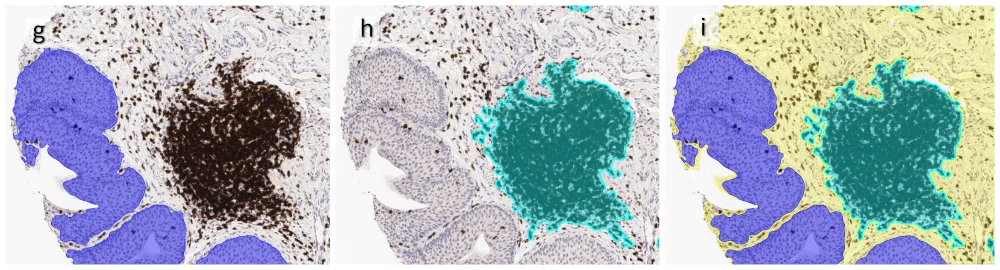

One of the most notable features of StrataQuest is the machine learning-based tissue classification. To train the algorithm, the user marks regions assigned to different tissues and trains the classifier on the sample; later this workflow can be used on other samples. The following images represent the outcome of the classifier: (g) epithelium is detected in blue; (h) displays the lymphocyte cluster in light blue. These algorithms (or masks) can be combined to achieve a better visualization: (i) epithelium is displayed in blue, lymphocyte cluster in light blue and stroma in yellow.

Beside the tissue classification itself, StrataQuest is capable of performing proximity analysis. It is possible to define specific proximity ranges; in the following case each range marked by different colors is 20µm. Nuclei detection was applied and CD3+ cells are shown in green, negative cells in yellow; (j) proximity ranges for the epithelium and (k) proximity ranges for the lymphocyte cluster.